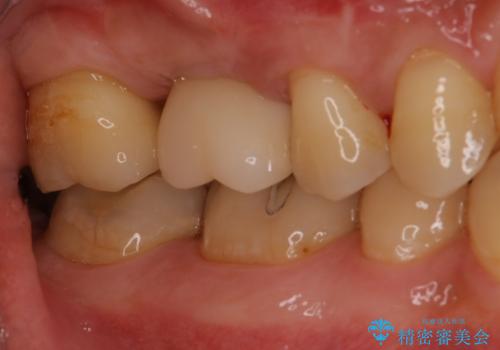

前歯をきれいにしたい 40代女性

- 前歯をきれいにしたいとのご希望で来院された患者様です。

他院でつけた仮歯がすぐとれてしまうとのことで困っていらっしゃいました。

残根状態の前歯は歯根破折により保存不可能と診断されたため、抜歯しブリッジによる補綴を行うことにしました。

このまま抜歯を行うと、ブリッジのポンティック部分の歯冠長が長くなり不自然になることが予想されたため、

抜歯前に歯の牽引(extrusion)及び抜歯時にソケットプリザベーションを行うことで歯肉のボリューム温存を図りました。

自然な仕上がりにご満足頂くことができました。

歯の牽引(extrusion)及びソケットプリザベーションによる歯肉のボリューム温存により、ブリッジの審美性・清掃性の向上が期待できます。

被せ物の種類:ジルコニアオールセラミッククラウン スタンダード